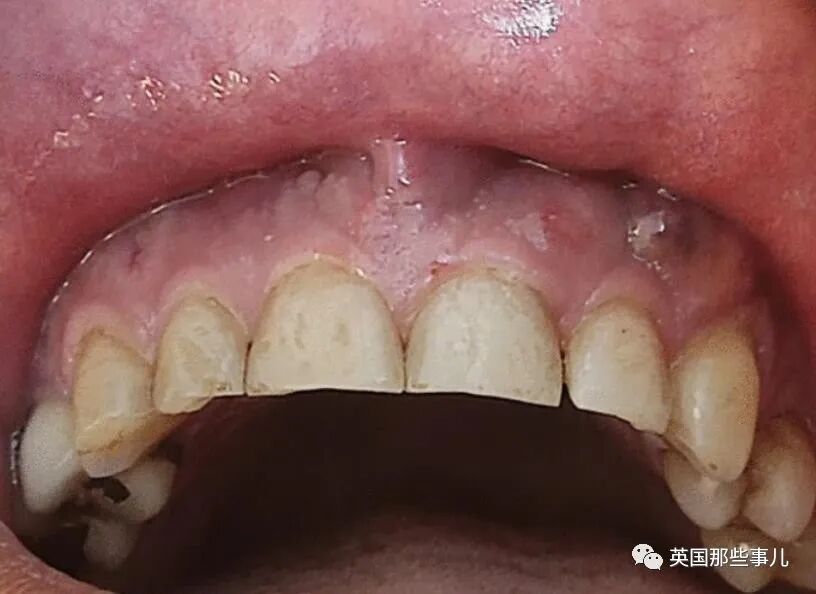

這回是因為頭疼和上頜區域出現疼痛,牙齦也有腫脹、流膿的情況,

3天後,患者的症狀仍然沒有緩解,上頜區域開始劇烈疼痛,牙齦有膿性分泌物。

他再次被轉診到牙周病醫生處,醫生發現他血糖壹直比較高,出現多發性牙齦膿腫,兩側上頜竇都出現明顯的陰影,鼻底和上頜竇壁也出現穿孔。- 新聞來源於其它媒體,內容不代表本站立場!